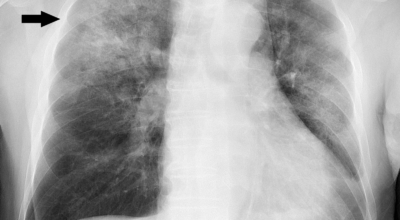

- 흉부 X선 촬영: 폐의 염증 부위를 확인하는 가장 기본적인 검사입니다.

- CT 촬영: X선 촬영보다 더 자세한 영상을 얻을 수 있어 폐렴의 위치와 범위를 정확하게 파악할 수 있습니다.